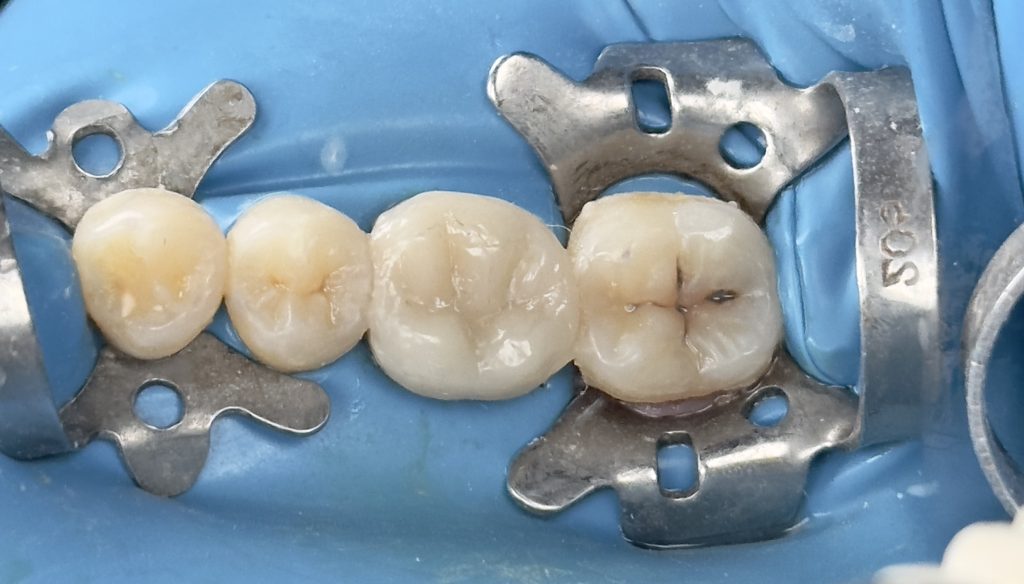

3rd visit :-

-Air abrasion of both tooth & restoration

-Cementation of the home made indirect composite

-Finishing &polishing